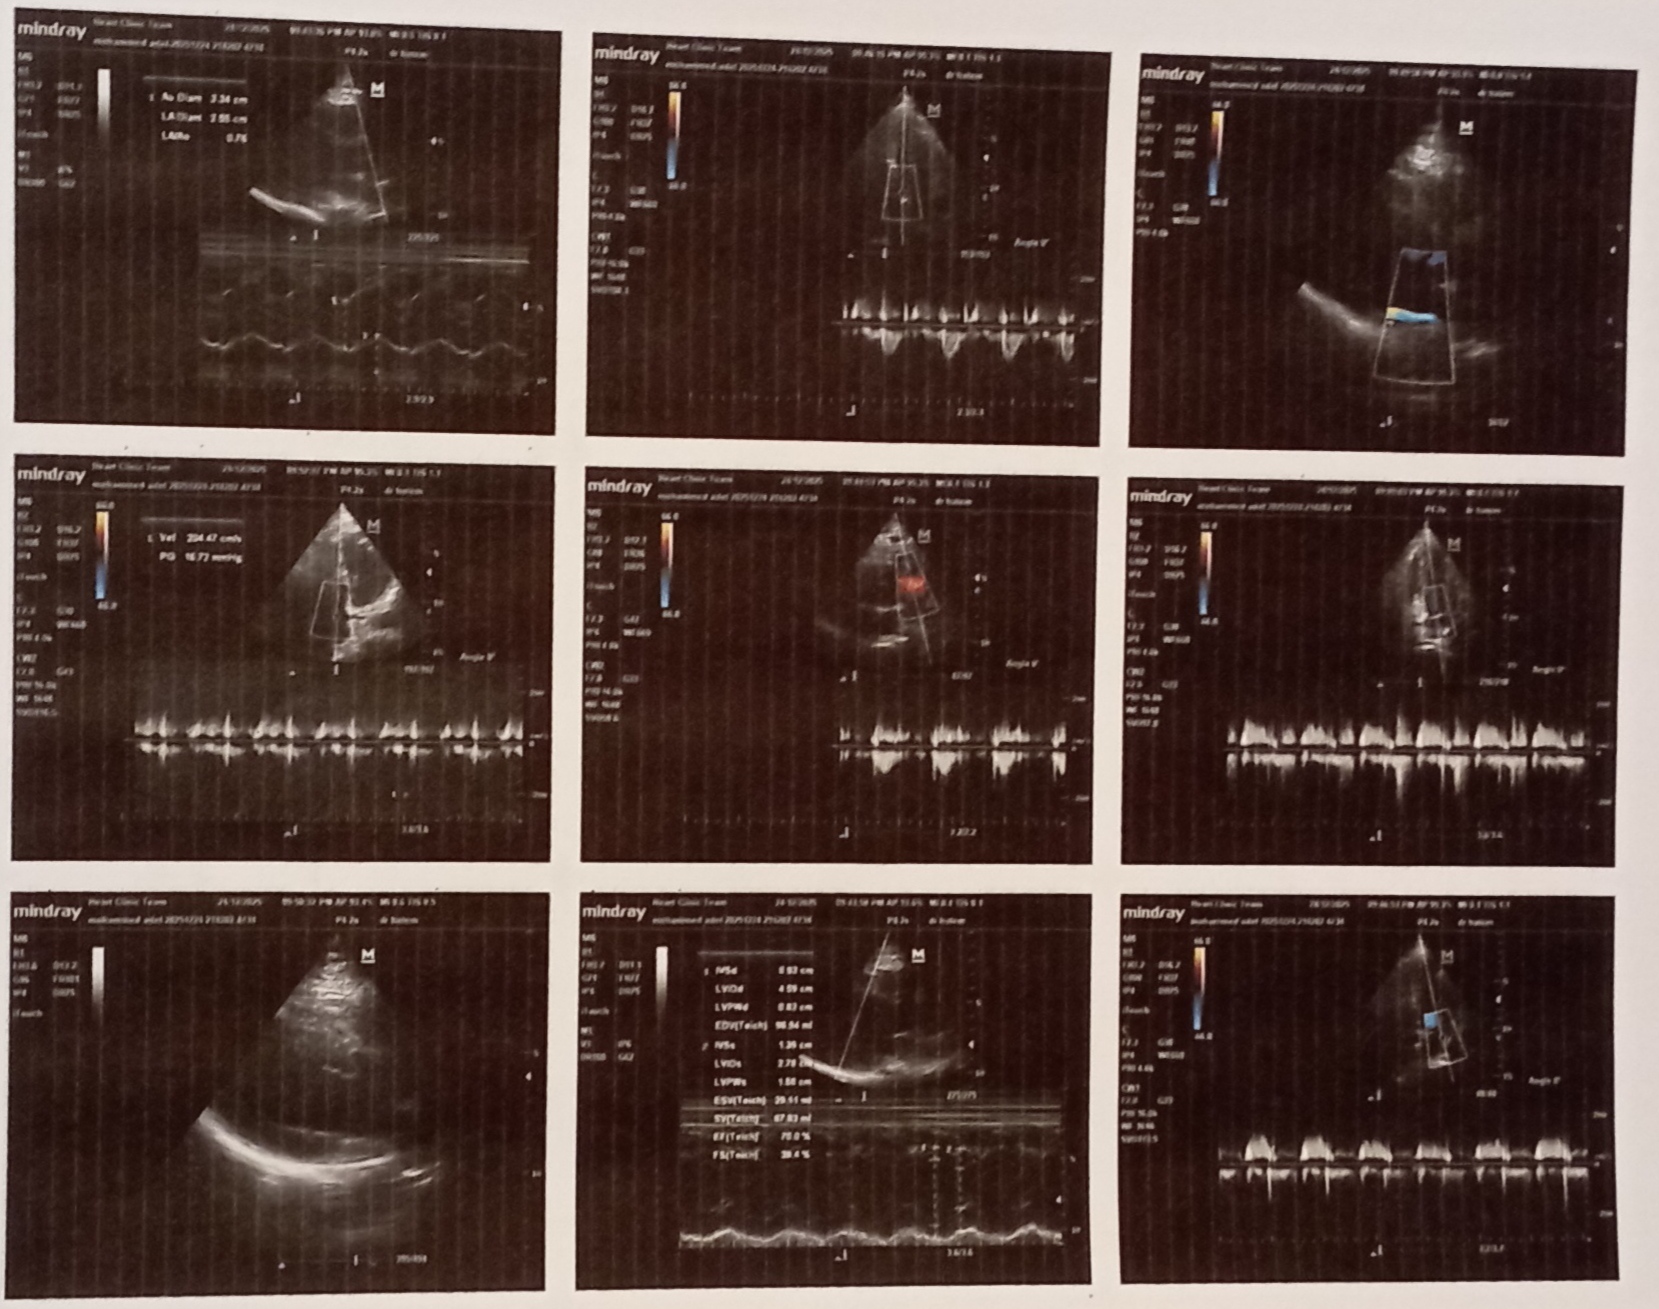

عندى ساعات ضربات قلب سريعة ولما رحت لدكتور قلب وعملت ايكو قالى انت عندك ارتجاع بسيط غير مركزى فى الصمام الميترالى وباخد كونكور 2.5 هل فى علاج للموضوع ده مع ان انا عديت شهرين والموضوع لسة زى ماهو ، اعمل ايه وهل فى مضاعفات لموضوع الارتجاع ده مع انى عامل ايكو ورسم قلب ياريت دكتور قلب موجود هنا يفيدنى